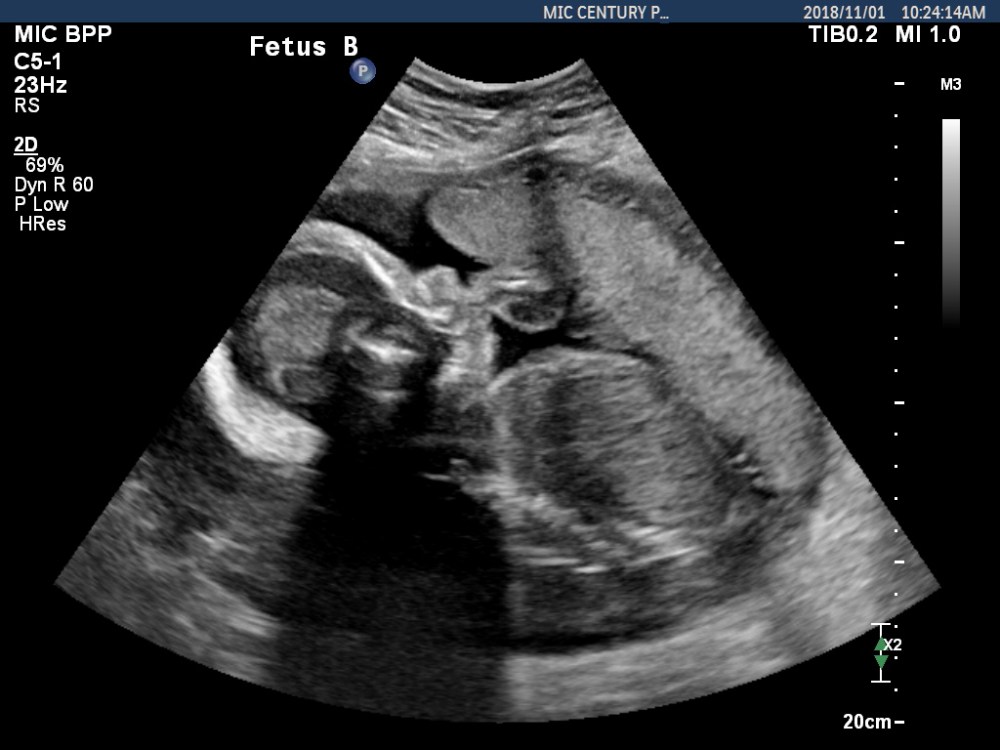

We have new baby photos! Auntie Pelican brought Alfalfa Sprout and Broccoli Sprout in for another ultrasound today to check their growth and all the other incredible processes that are unfolding as the date we meet our children approaches.

Each baby is now a full two pounds. Two pounds. Each. That is a full four pounds of beloved family members, and that mass is climbing daily.

I am elated to share that our wee ones continue to look just as they should. Both babies are right on track for size and development, and the current estimate puts Alfalfa fewer than 30 grams heavier than their sibling. This is fantastic news in a twin pregnancy, since it suggests both fetuses are receiving adequate nutrients and oxygen.

Check out these tiny people: